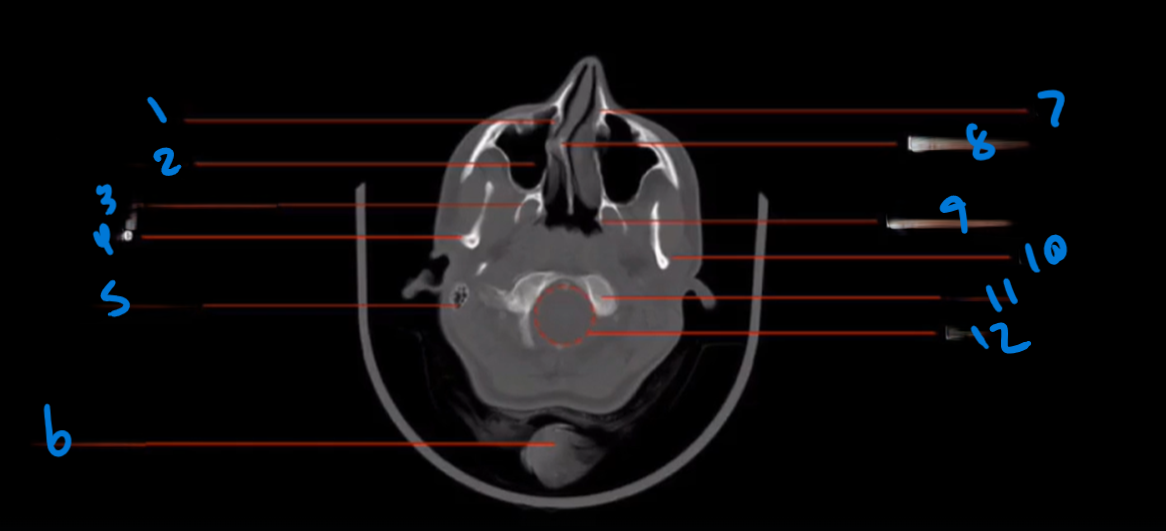

Landmark 1

Lacrimal Duct

Landmark 2

Maxillary Sinus

Landmark 3

Lateral Pterygoid Process

Landmark 4

Mandible

Landmark 5

Mastoid Air Cells

Landmark 6

Pony tail

Landmark 7

Maxilla

Landmark 8

Deviated Nasal Septum

Landmark 9

Medial pterygoid Process

Landmark 10

Landmark 11

Occipital Condyle

12

Foramen Magnum